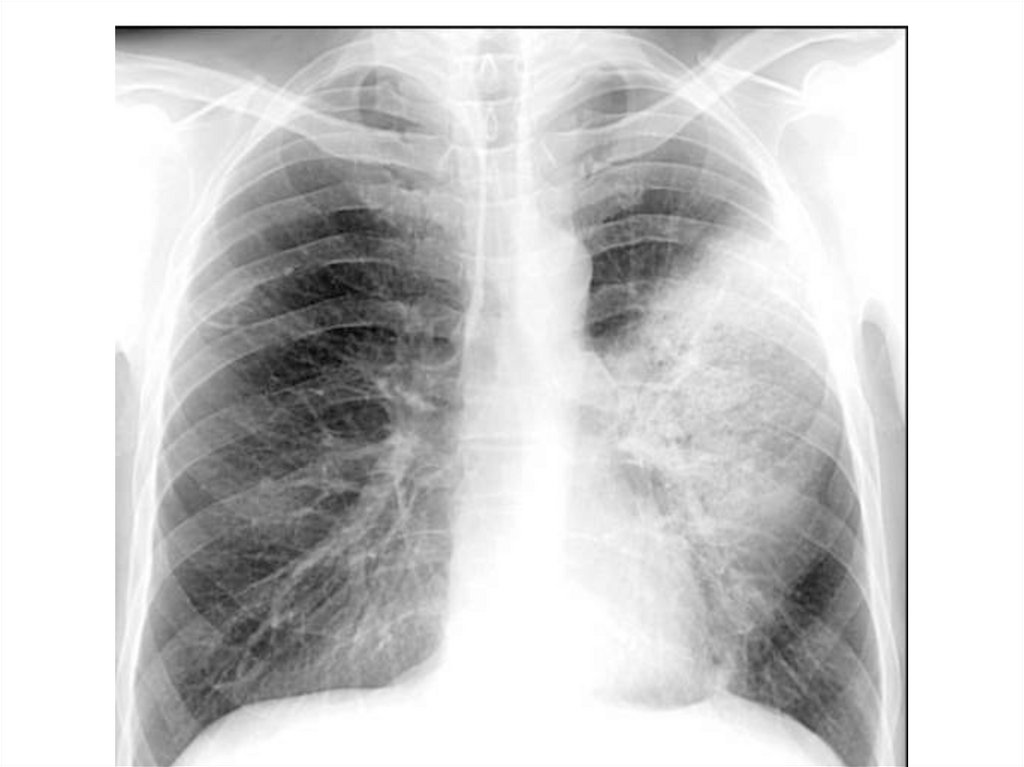

Пневмония

Экссудативный плеврит